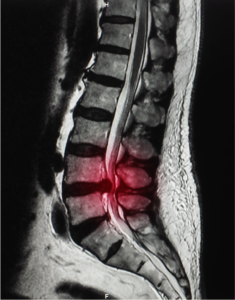

lumbar degenerative disc disease

Lumbar degenerative disc disease (DDD) is a common cause of low back pain. The vertebrae are cushioned by intervertebral discs…